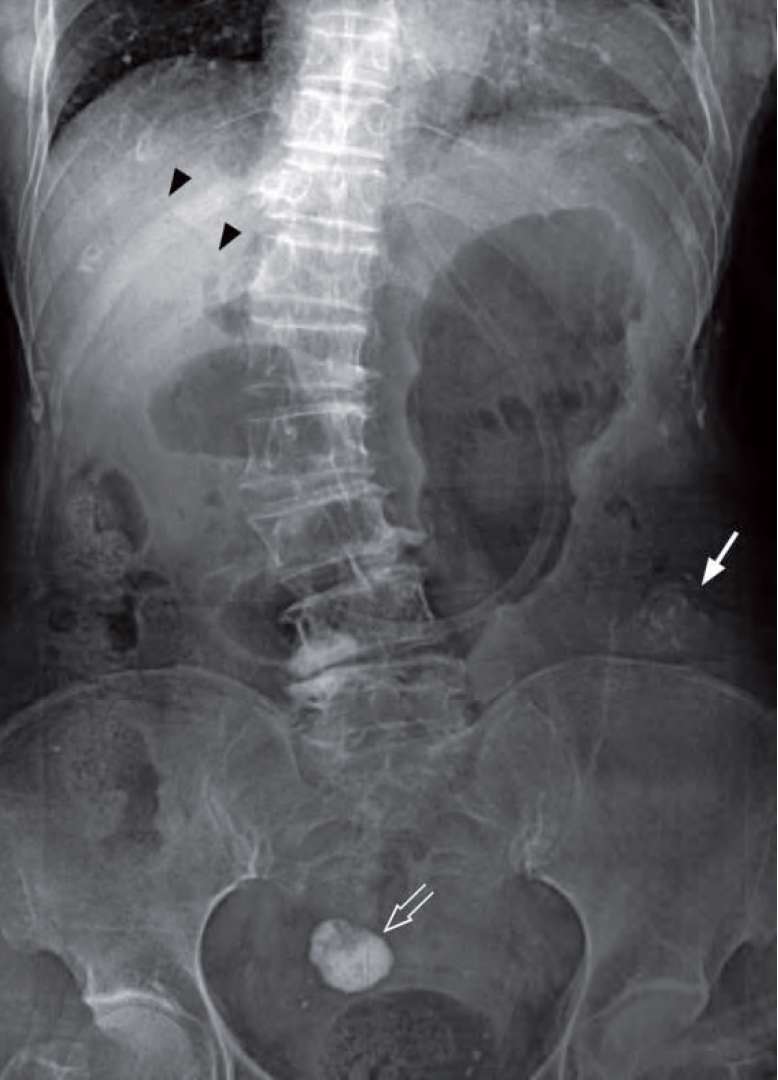

A 70-year-old woman with a known history of gallstone disease, complained of colicky abdominal pain, vomiting, abdominal distension and constipation for three days.

Physical examination showed a distended abdomen with hyperactive bowel sounds on auscultation. No focal peritoneal signs were present on palpation. Per rectal examination showed an empty rectum. Laboratory investigations were unremarkable. The clinical diagnosis of intestinal obstruction was made and a supine AXR performed.

What radiological abnormalities can you see and what’s the diagnosis ?